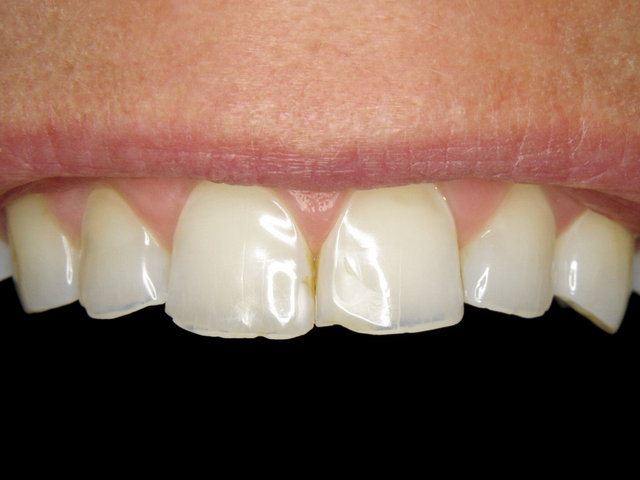

Säuregeschädigte Zähne ...

Composit-Verblendung by CLINICDENT ✓